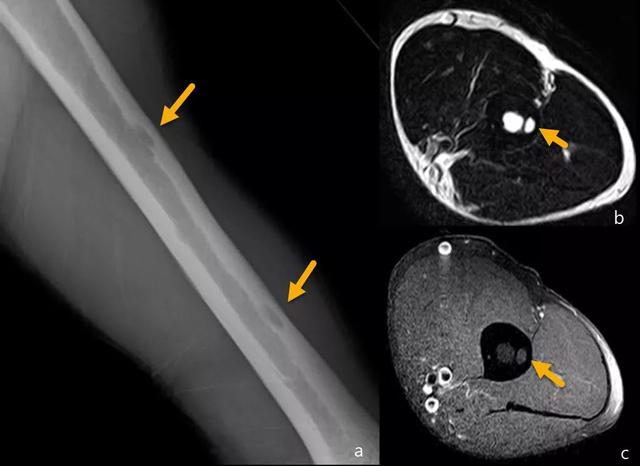

射线照相外观是一种局部性溶解病变,边界明确,具有皮质破坏,软组织肿块和无骨膜反应(图18)。

图18:15年前用固定治疗的胫骨干骨折,愈伤组织区的疼痛性溶解性病变(a和b)。病变是扩张的,皮质中断,伴有相关的软组织成分(c)。在扩展研究中,在左髂骨中观察到另一个具有相似特征的病变(d)。胫骨病变活检的结果是多灶性上皮样血管内皮瘤。